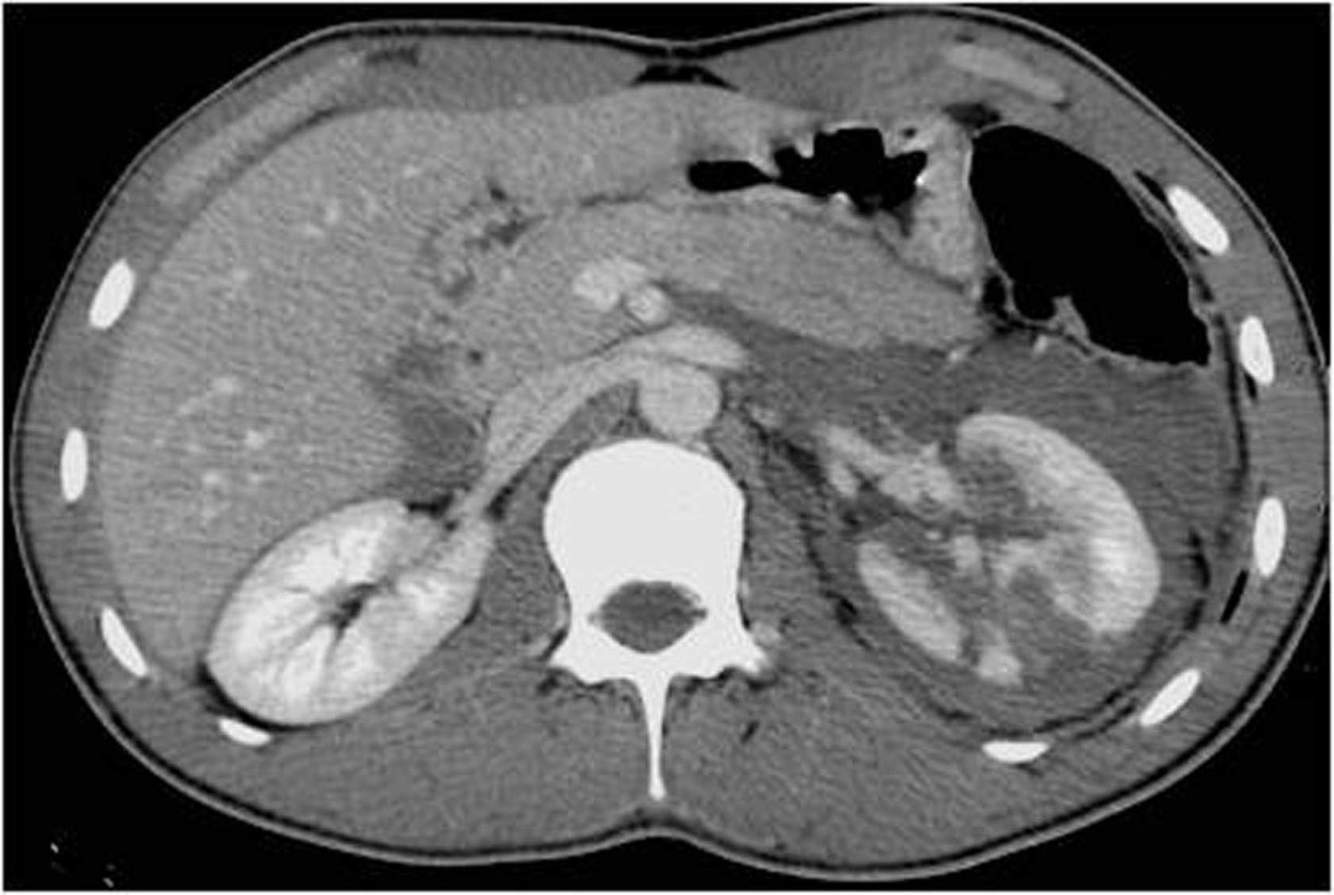

This is a CT of a motorcyclist hit by a car. What injury does the abdominal CT show?

a) Penetration of the abdominal wall

b) Splenic laceration

c) Liver laceration

d) Kidney laceration

e) Lumbar vertebra fracture

A